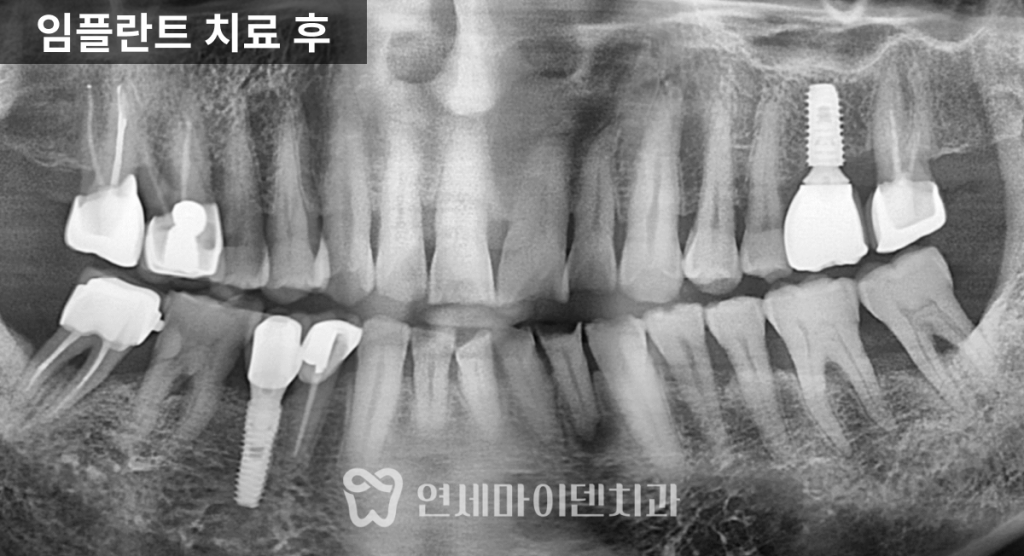

안정성을 높였습니다.건강보험 임플란트 최종 보철

수술 부위가 안정된 이후에는

환자분에게 맞는

맞춤형 지대주를 이용해

보철물을 제작했습니다.과거 건강보험 임플란트 보철은

금속과 도자기를 결합한

PFM 크라운만 가능했지만,최근에는

지르코니아 크라운까지 보험 적용이 확대되면서

심미성과 내구성이

모두 개선되었습니다.

지르코니아 크라운은

인공 다이아몬드라 불리는

지르코니움 재질을 깎아 제작하며,

치과용 세라믹 재료 중

강도가 매우 높고

심미성 또한 우수한 재료입니다.금속 성분이 포함되지 않아

어금니와 앞니 모두에